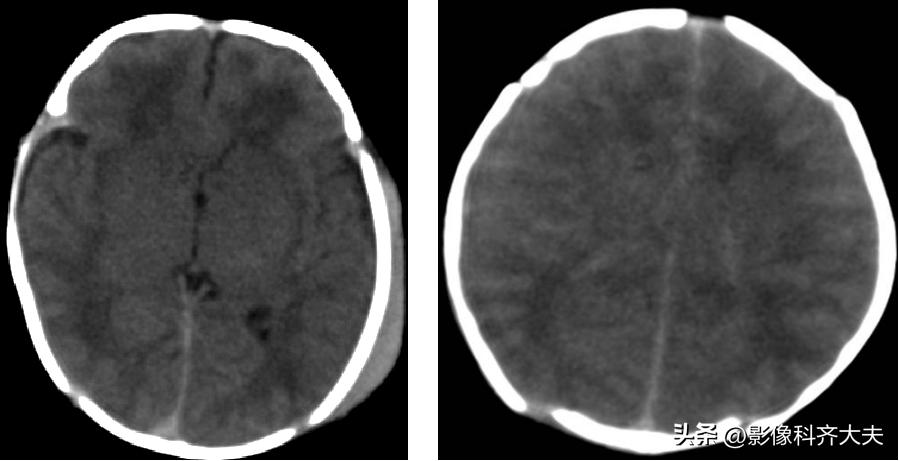

HIE的CT表现

1、测定脑实质的CT值,正常足月儿脑白质CT值在20Hu以上,≤18Hu为低密度

2、脑水肿时呈双侧大脑半球呈弥漫性低密度伴脑室变窄

CT分度

1、轻度:散在局灶低密度影分布2个脑叶内。

2、中度:低密度影超过2个脑叶,白质灰质对比模糊。

3、重度:弥漫性低密度影,灰质白质界限消失,但基底节、小脑尚有正常密度。

注:中、重度常伴有颅内出血。